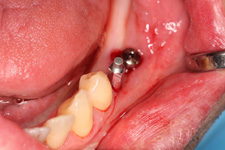

V našem zařízení používáme při zavádění implantátů tzv. počítačem podporované implantace. V současnosti se jedná o dva postupy

• Navigovaná implantace - navigated surgery - dynamická navigace

- operace je "z volné ruky" a postup se vizuálně kontroluje na monitorech.

• Řízená implantace - guided surgery – statická navigace

- operace pomocí OP šablon. Ve speciálním programu coDiagnostiX se využívají data z CB CT scanu - tedy údaje o množství a kvalitě kosti, dále data získaná ze scanu modelu čelistí s modelem plánované protetické náhrady (korunky, můstku…)

- tedy údaje tloušťce sliznice, pozice a tvaru náhrady.

Tím máme všechny potřebné údaje pro plánování pozic implantátů, jejich potřebné délce a průměru. Abychom mohli implantáty zavést do naplánovaných pozic v ústech pacienta, umožňuje tento program vymodelovat speciální operační šablonu, která je zhotovena 3D tiskárnou. Pomocí této šablony, která se umístí do úst pacienta, pak probíhá vlastní operace

- zavádění implantátů.